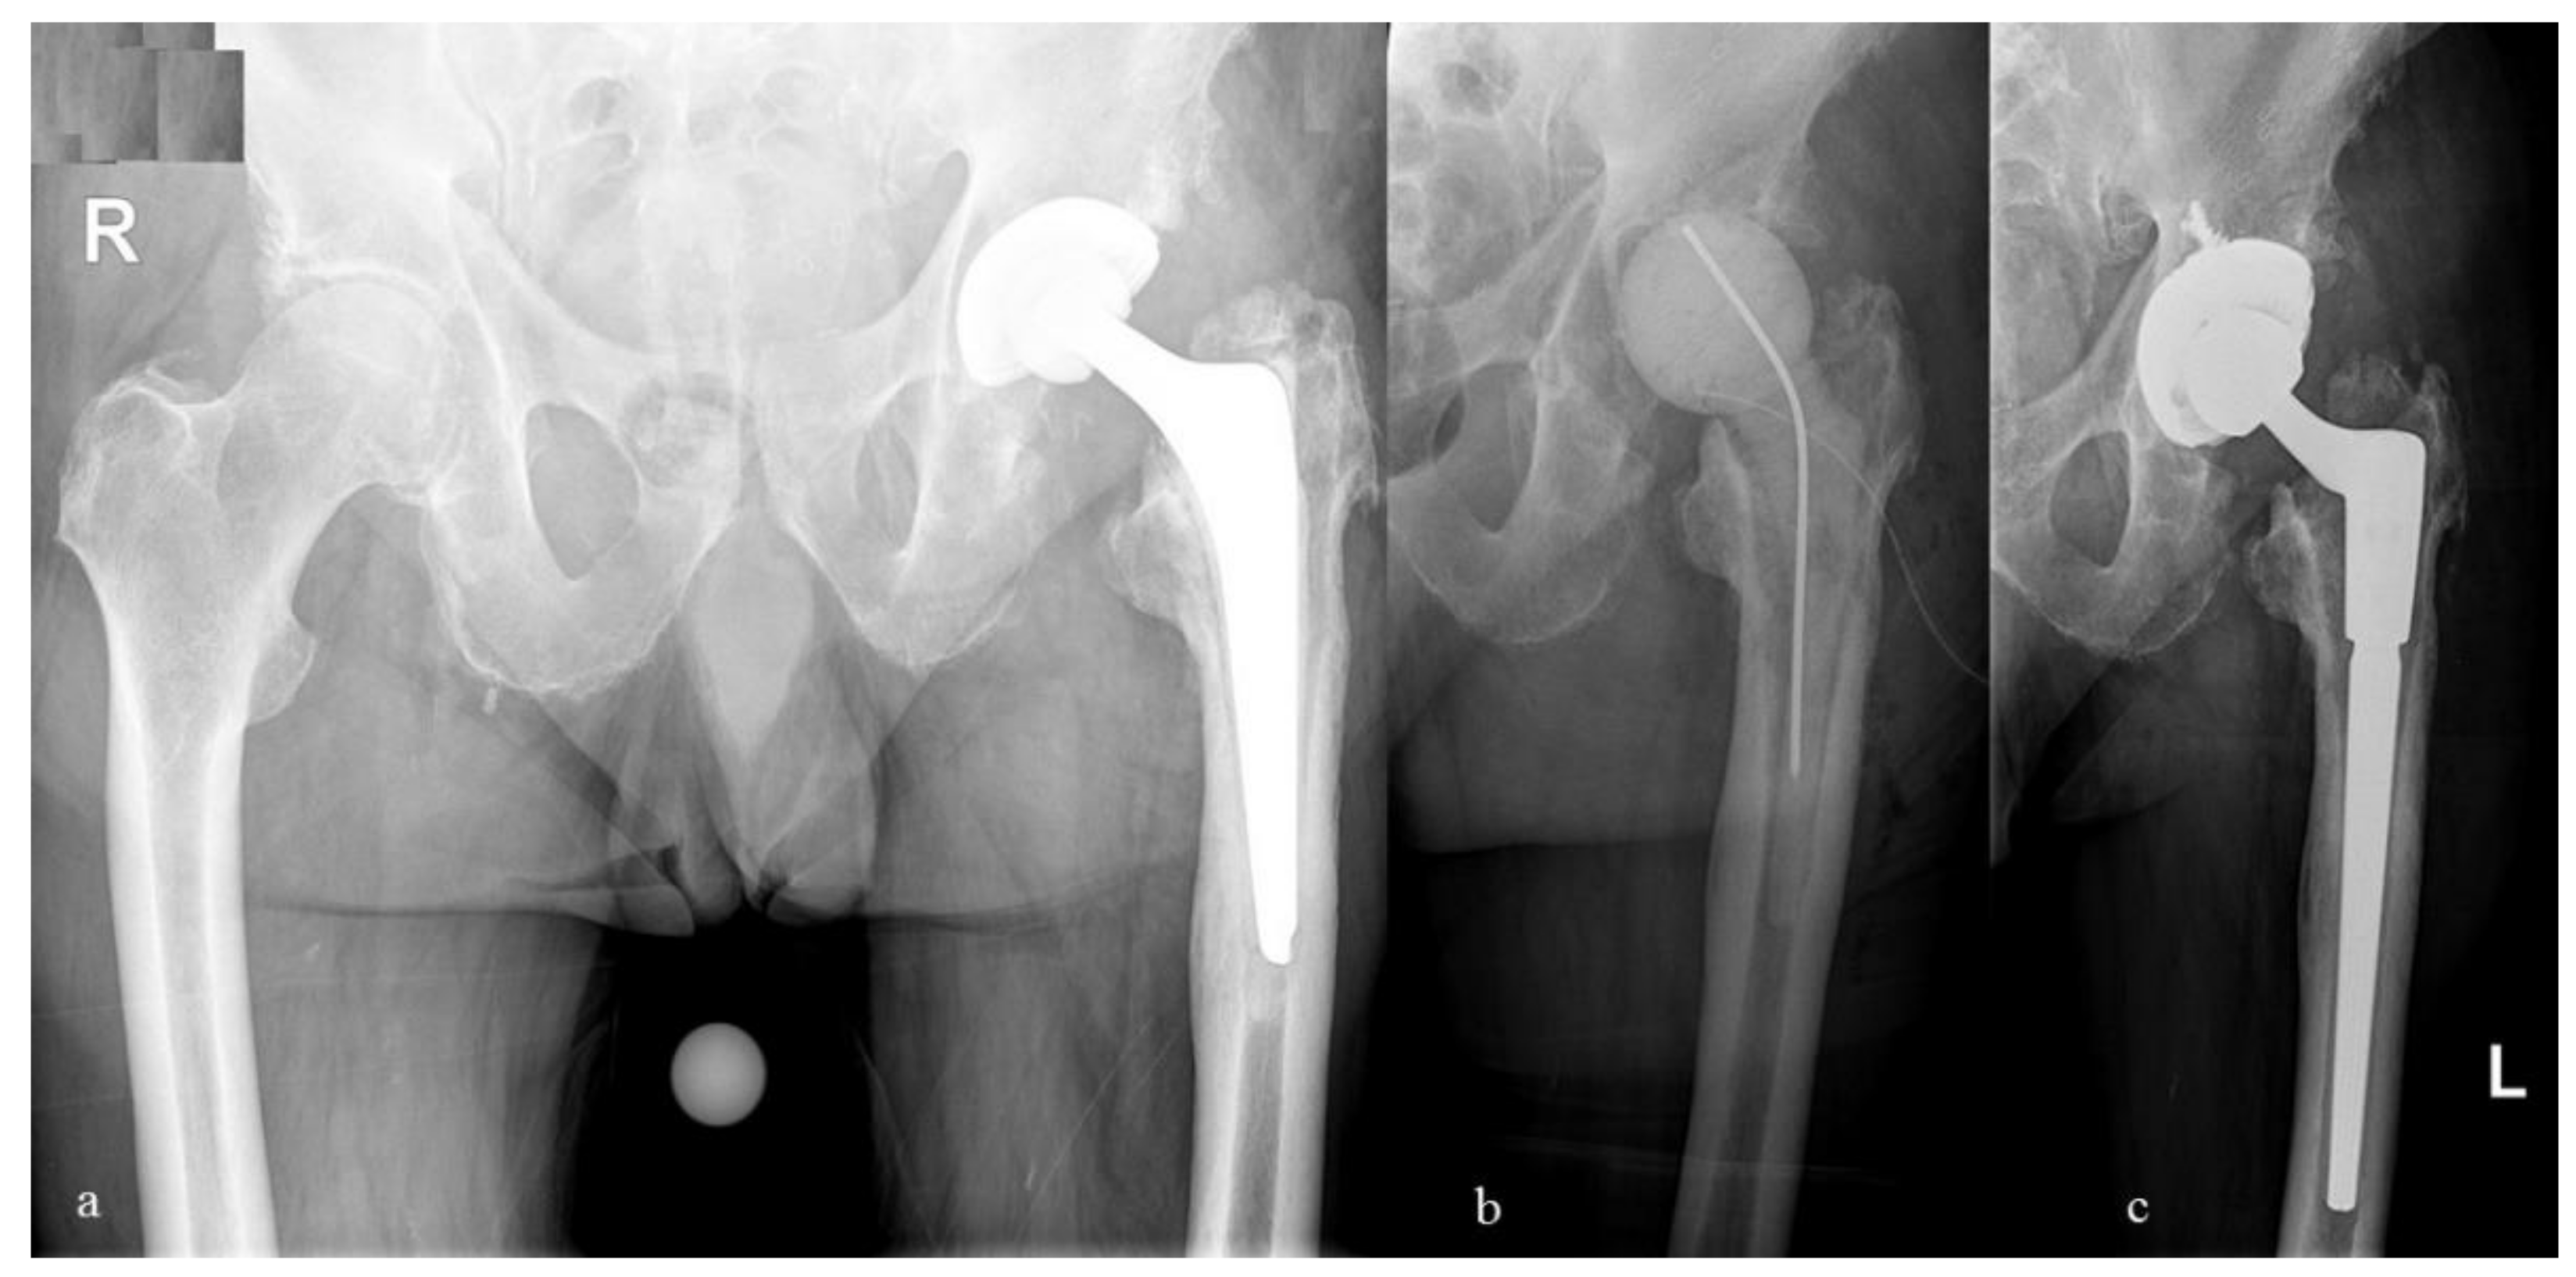

2.3. Antibiotic Impregnation of the Spacers/Beads and Resistance Rates

2.4. Clinical and Infection Outcome